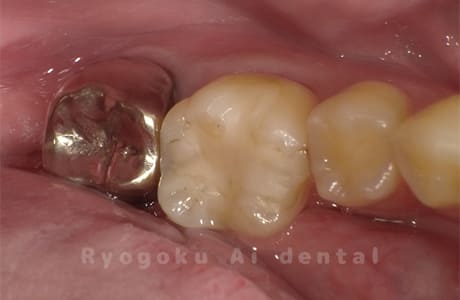

Case27

歯牙移植術直後咬合面

-

歯牙移植術後咬合面

歯牙移植術前側面

歯牙移植術中側面

歯牙移植術後側面

- 原因

- 重度カリエス

- 治療内容

- 自家歯牙移植、部分矯正

- 治療費用

- 220,000円(移植費用)

110,000円(部分矯正費用)

虫歯が大きく、保存不可能となった歯を上の親知らずと交換する自家歯牙移植を行いました。移植歯が小ぶりであったため、部分矯正を行い問題なく噛み合い、経過良好です。